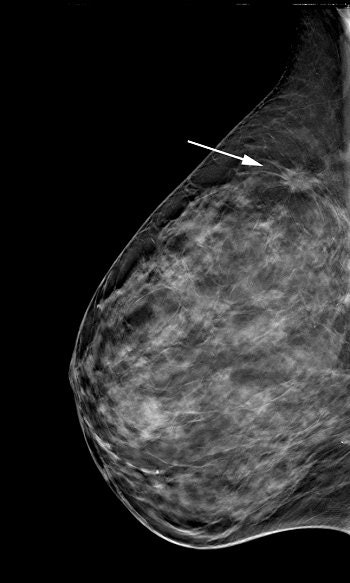

| Tubulolobular adenocarcinoma seen on conventional digital mammogram (left) and in a slice from a tomosynthesis dataset (right). Image courtesy of Hologic. |

The results showed that the ROC curve was superior for DBT compared to FFDM alone for all 12 readers, with the area under the ROC increasing by 0.071 using the BIRADS scale and 0.072 using the probability of malignancy scale. DBT had a sensitivity of 76.2% versus 65.5% for FFDM alone and a specificity of 89.2% versus 84.1%. The mean recall rate was reduced by 42.6%.